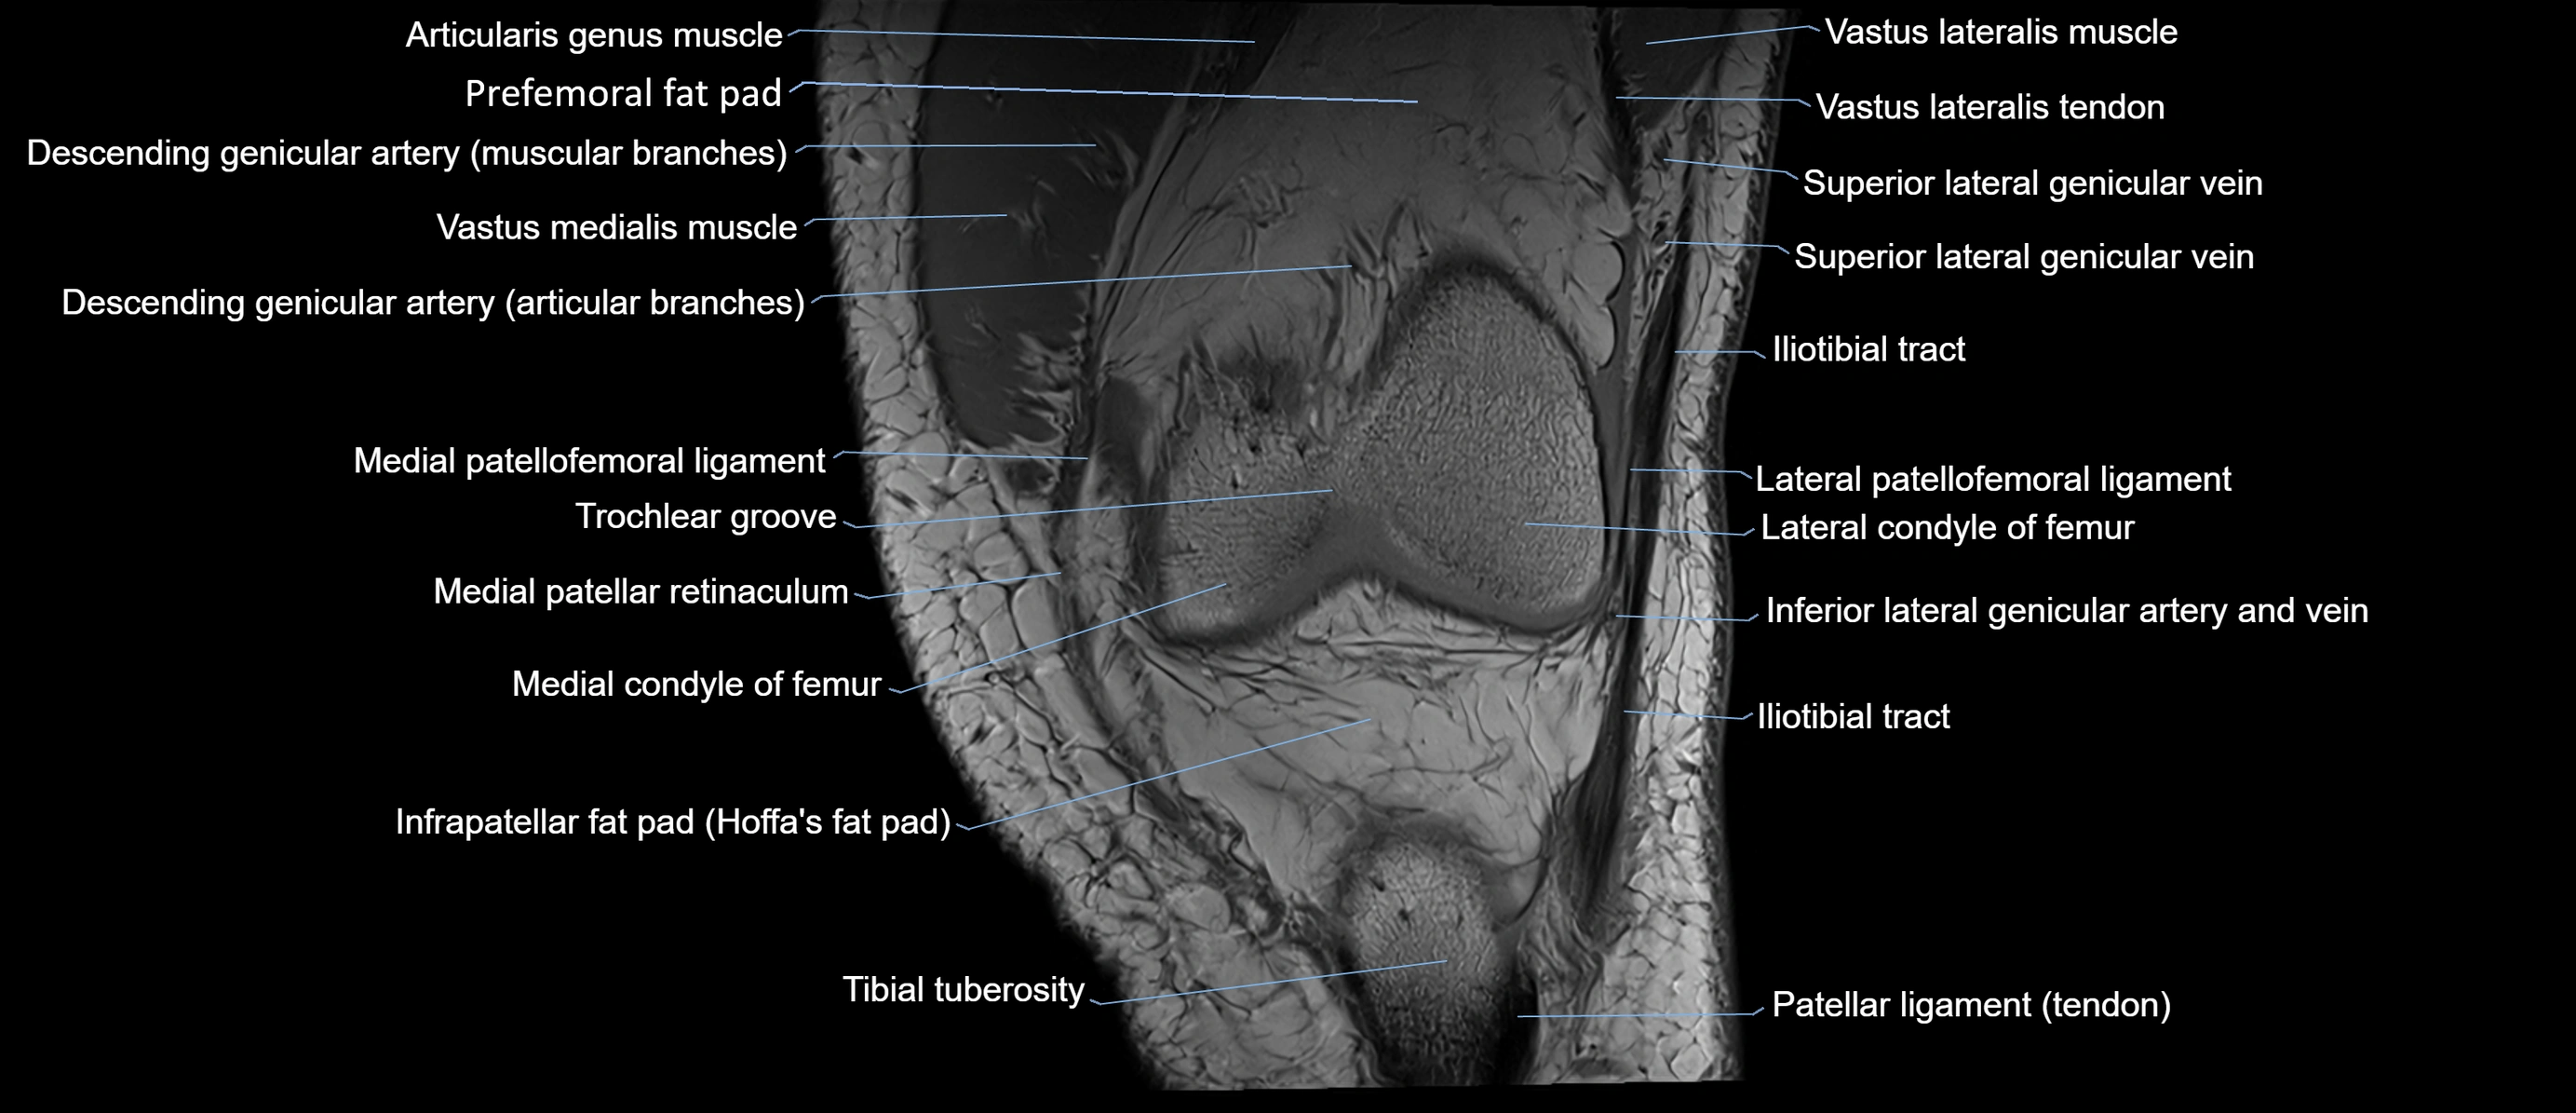

- Knee Joint

- Lateral condyle of femur

- Lateral patellofemoral ligament

- Medial condyle of femur

- Medial patellar retinaculum

- Medial patellofemoral ligament

- Patellar tendon (patellar ligament)

- Prefemoral fat pad

- Tibial tuberosity

- Trochlear groove